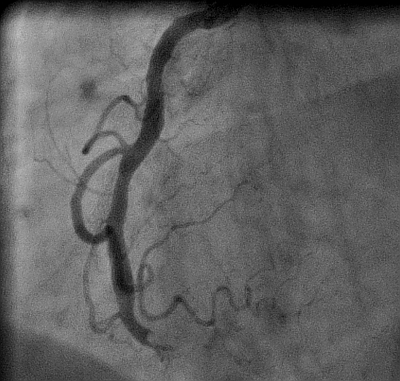

Angioplasty LAD With Severe CAD

Angiogram, Angioplasty of LAD, Coronary artery disease image

This image is taken from the patient featured in our Teaching Series, AWMI.  This shot shows the left anterior descending artery just after a stent has been placed and blood flow returned.  There had been a 100% occlusion prior to the angioplasty.  The circumflex and obtuse marginal arteries show evidence of severe coronary artery disease and multiple partial obstructions, and were also repaired.